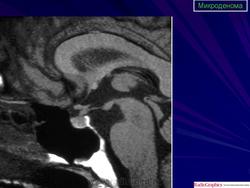

ГМ. Аденома гипофиза 1. +

Аденома гипофиза.